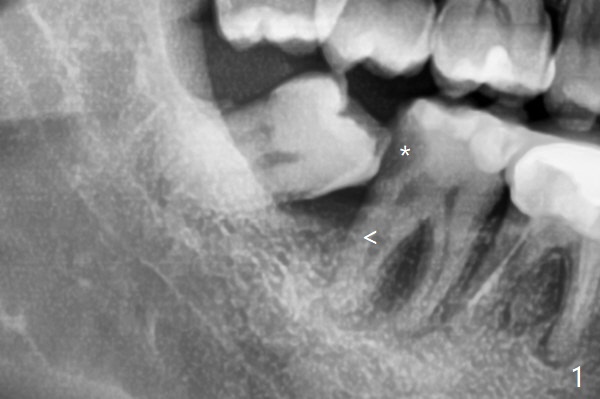

当57岁男因右下7龋齿夜间痛(图一:*),远中骨质吸收(<)就诊时,提出拔除8后放置粘性骨粉和PRF,他欣然同意。拔除智齿(没去骨,但是劈牙)后,7远中去龋,临时充填(图二:*(IRM,必要时转诊根管治疗))。为了让粘性骨粉在最关键部位(7远中)发挥作用,放置前在牙槽窝根尖放置胶原塞(C),占据空间,后来发现骨粉量足够。